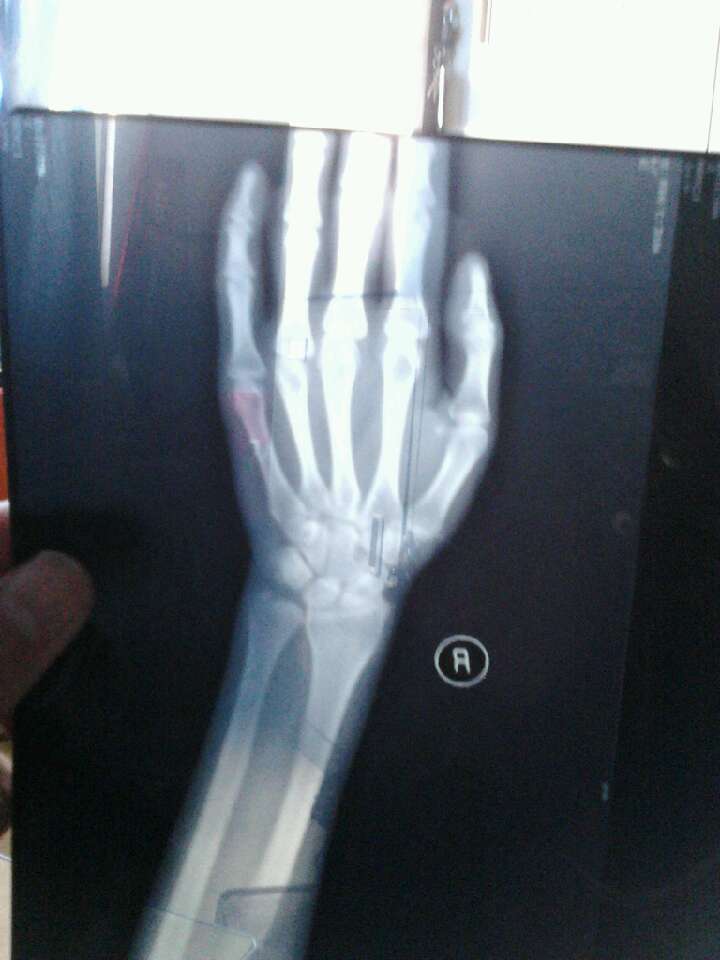

尺骨茎突游离,是这个名字···这是现在的状态.

右手尺骨茎突骨折

b茎突尖端,c尺骨茎突,d尺骨头,e尺骨颈,f尺骨干远端,q1尺骨茎突骨折